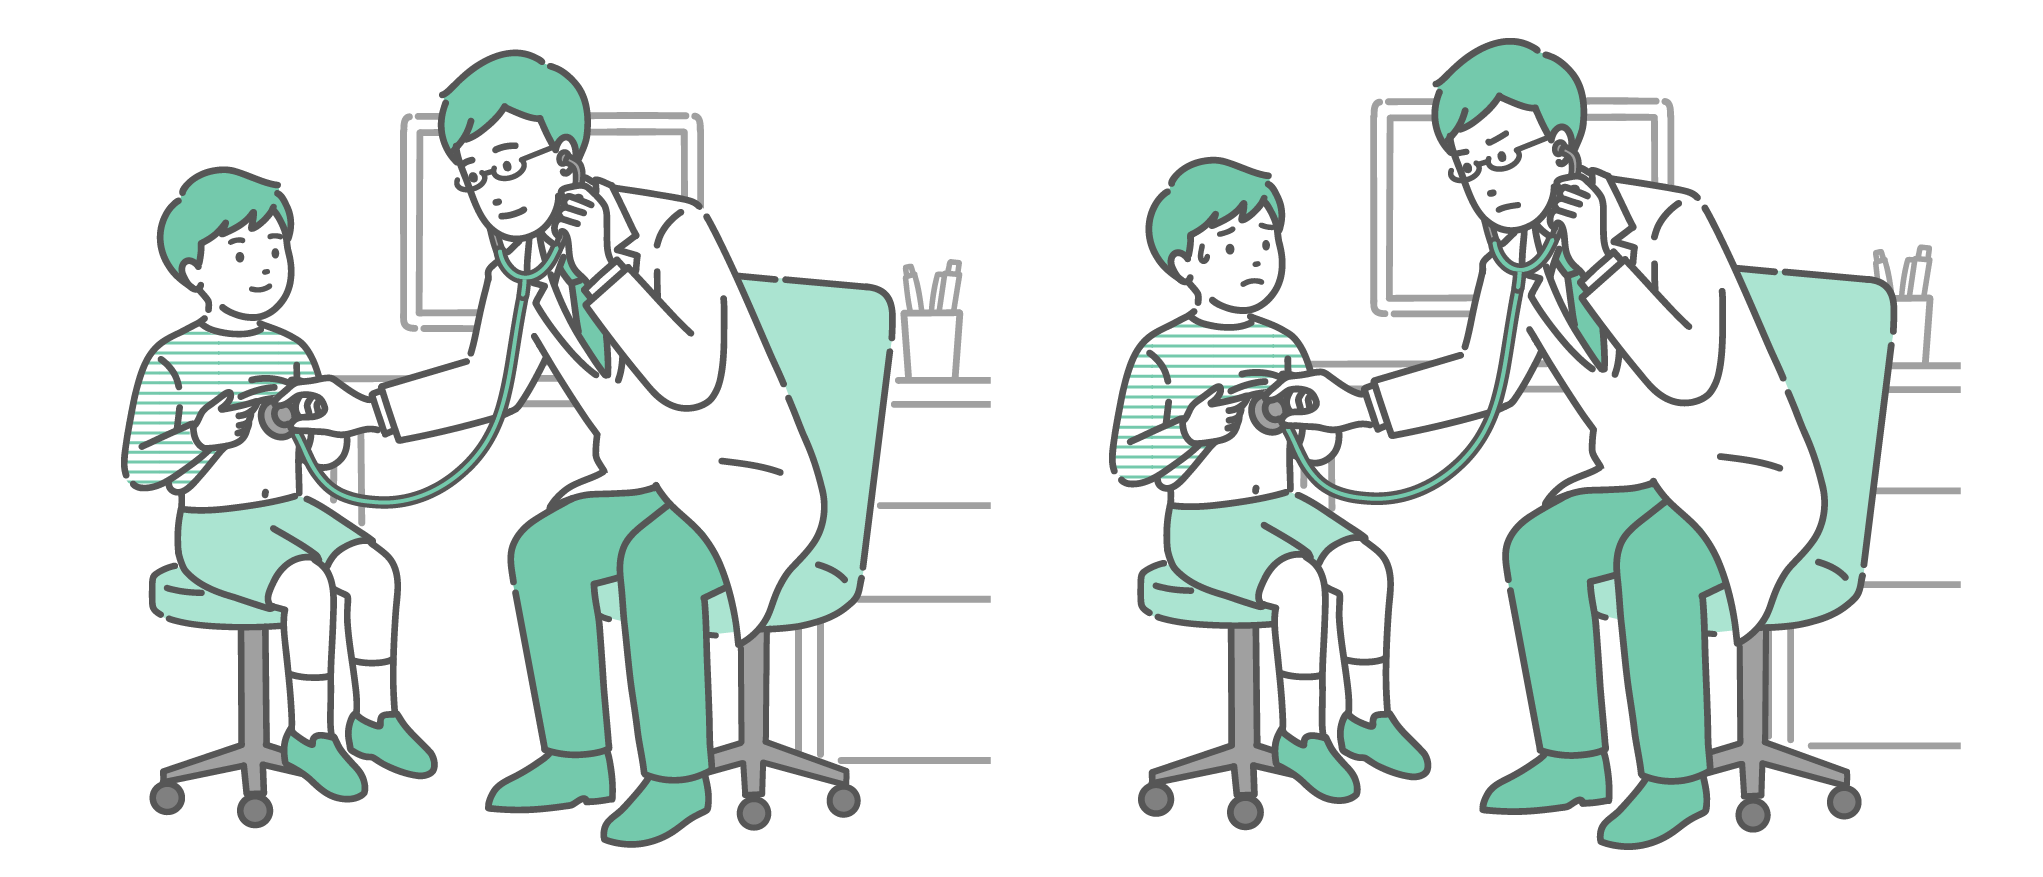

小児科・子供の健康 聴診器で診察する男性医師のイラストセット(白衣・男の子・通常と体調不良)